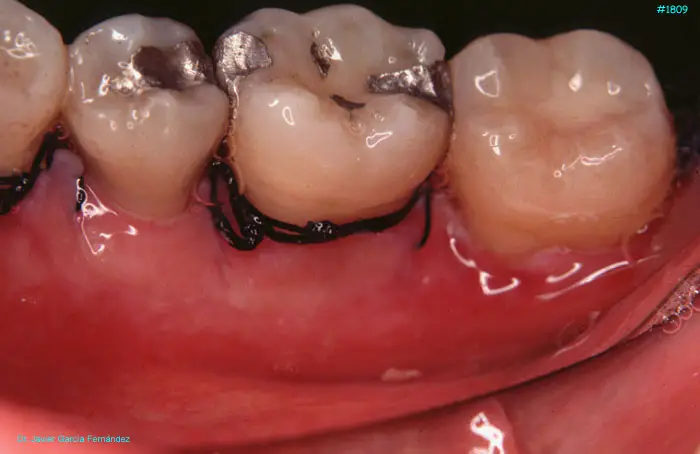

image 75